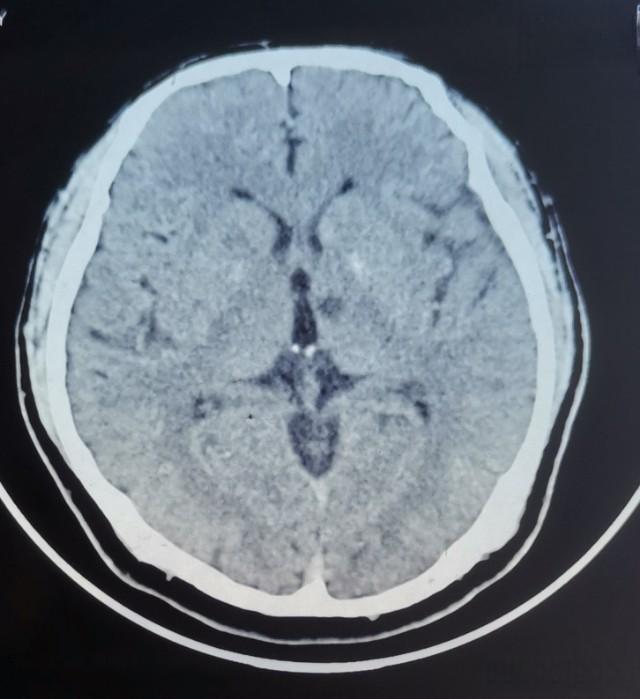

在一次例行体检中,50岁的张先生意外发现自己患有腔隙性脑梗死。这个诊断让他大吃一惊 - 他从未感到任何不适,日常生活也没有受到影响。然而,医生告诉他,这个看似无害的发现可能潜藏着巨大的健康风险。

腔隙性脑梗死,简称腔梗,是一种常见的脑血管疾病。它通常由高血压、糖尿病等因素引起,导致大脑深部的小穿通动脉闭塞,形成直径在0.2到20毫米之间的病灶。据统计,腔梗占所有缺血性中风的25%,年发病率约为每10万人中15人。